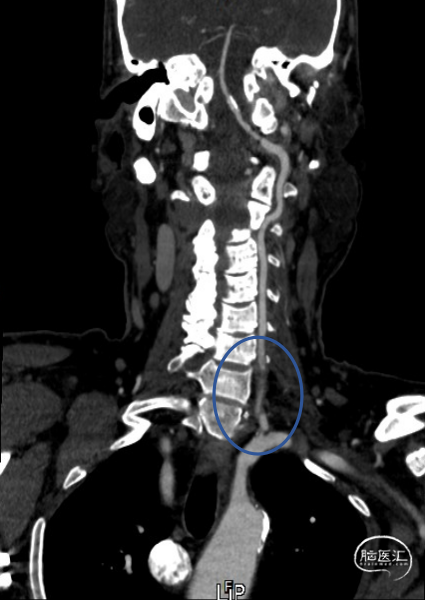

➢头颈部CTA(三维重建MIP像)

➢头颈部CTA(原始像)

患者于入院前10天突发视物重影,5分钟左右缓解,当晚18:00出现颈后不适伴左上肢持续性麻木,10天后来我院急诊神经内科就诊,就诊时测血压191/93mmHg,自行服用拜新同1粒。 完善头颅MRI:桥脑、两侧小脑急性缺血性梗塞;右侧基底节软化灶;两侧侧脑室旁少量白质疏松;老年脑改变。 入院后予药物保守并完善头颈部CTA:左侧颈内动脉虹吸段多发钙化斑块、混合斑块,管腔轻-中度狭窄,C7段小动脉瘤。右侧颈内动脉虹吸段多发钙化斑块,管腔轻度狭窄。右侧椎动脉纤细,V4段局部显示欠清。左椎V1、V2段非钙化斑块,局部管腔重度狭窄-闭塞,V4段钙化斑块,管腔中度狭窄。右侧部分型大脑后动脉,P1段重度狭窄,P2段中度狭窄。双侧大脑中动脉M2段中至重度狭窄。 告知患者病情存在进一步进展可能,患者家属商量后要求手术治疗。

术前影像考虑右侧孤立椎,左侧椎动脉V1段重度狭窄、狭窄段以远扭曲成襻且合并长节段多发动脉粥样硬化狭窄改变(夹层待排),同时左椎V4段局部重度狭窄可能;